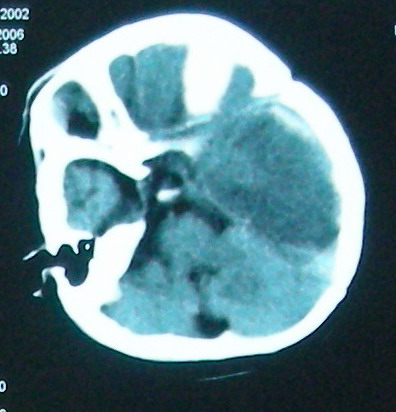

结合临床考虑1、脓毒栓子致左侧大脑半球及右侧额叶梗塞。2、左侧额颞顶部硬膜下血肿形成.3、镰下疝形成。

硬膜下出血、蛛网膜下腔出血(至于病因,可能与外伤有关,慢性出血的可能性比较大。但应该不是产伤所致?)--上矢状窦内血凝块 --静脉回流不畅或受阻--进而形成左侧大面积水肿和梗塞。临床有高热,感染所致 脓栓栓塞血管不排除,但它不好解释为什么会有硬膜下出血。